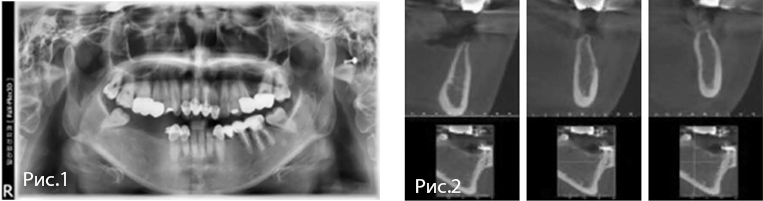

Рис. 1—2. Исходная рентгенологическая и клиническая картина.

Рис. 3—12. Оперативное вмешательство. Послеоперационная панорамная рентгенограмма.